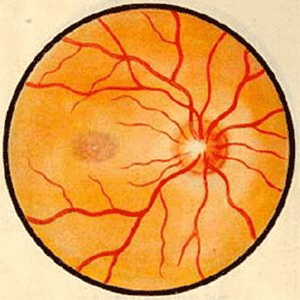

视神经病变

太阳成tyc122cc学术资讯:脉络膜新生血管医治 评估的思考